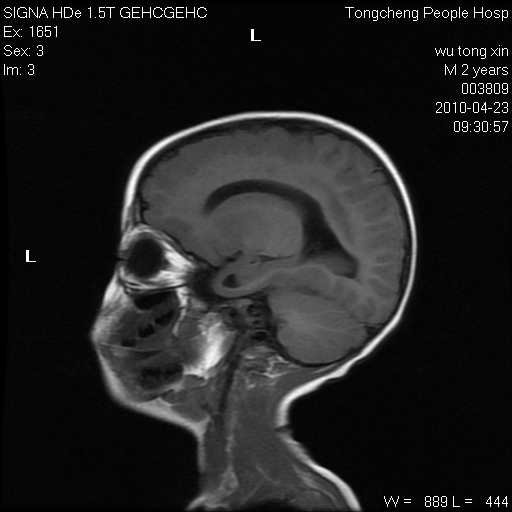

以下是引用赵物学在2010-4-25 12:43:00的发言:[br]巨脑回[br]侧脑室后角低密度影考虑hie或肾上腺脑白质营养不良?[br][br][本贴已被 赵物学 于 2010-4-25 12:51:28 修改过]

以下是引用gaoxiao在2010-4-25 16:54:00的发言:[br]巨脑回畸形。脑白质髓鞘化不良

以下是引用pujunzhi在2010-4-25 21:35:00的发言:[br]考虑 1双侧大脑皮质发育不良 2轻度脑积水 3双侧脑室后角旁片状长t1长t2信号,需继续观察,因为正常小儿此处脑白质的髓鞘化时间可以延迟到4-6岁,才显示正常。